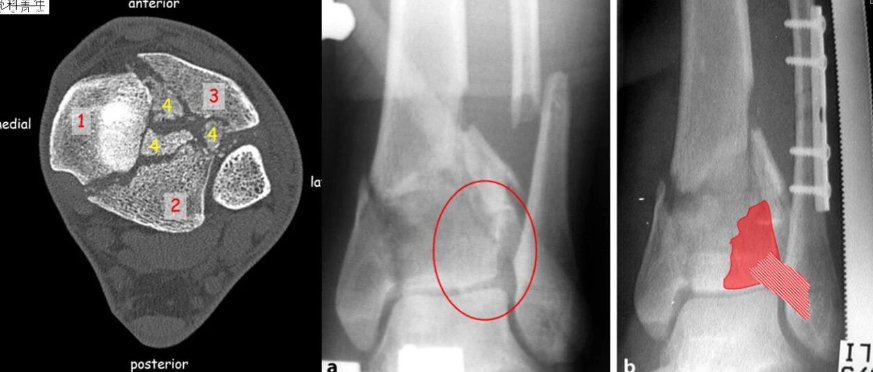

腓骨髓内钉固定减少一个切口可行吗?

1分钟

5.8万人学习